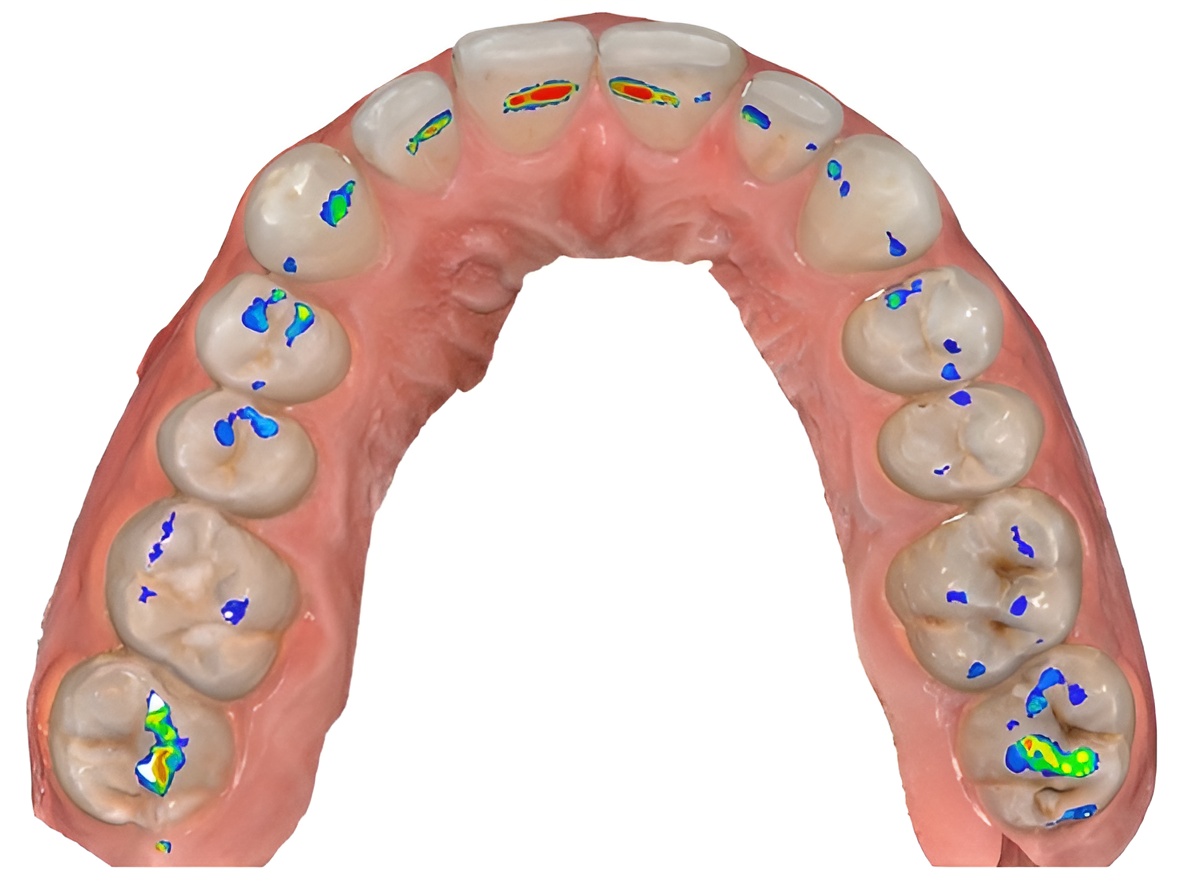

Intelligence artificielle

2 examensExamens disponibles

AI #2

Intelligence artificielle #1